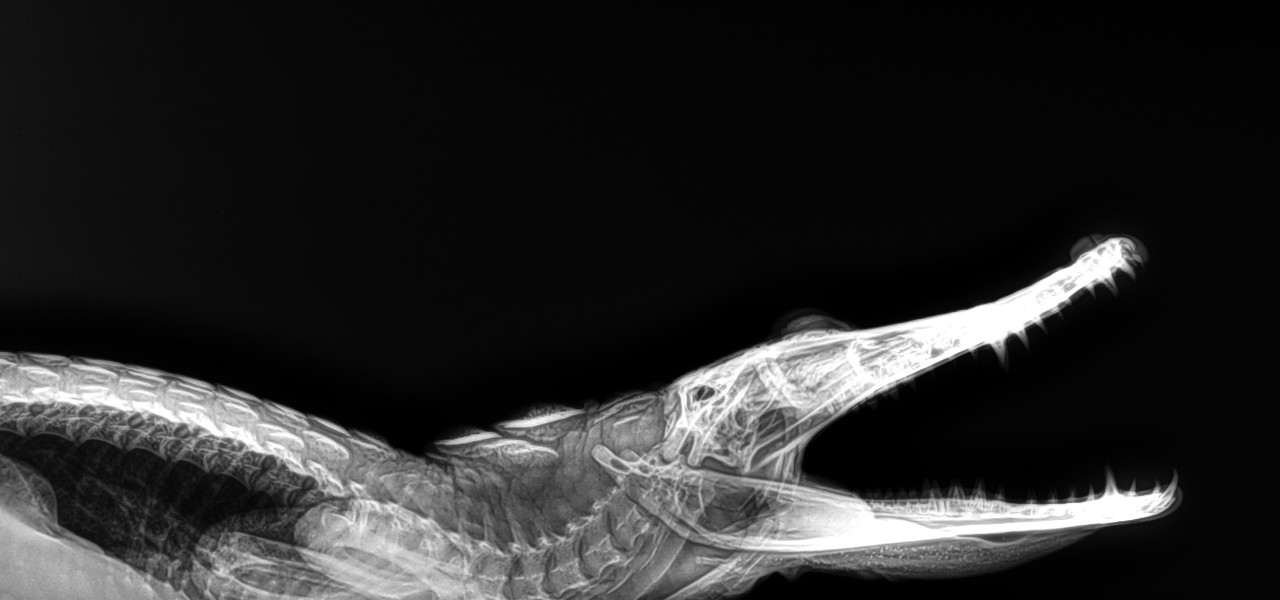

Radiología Digital Directa en

Animales

• Caballos

• Pequeñas especies

• Animales exóticos